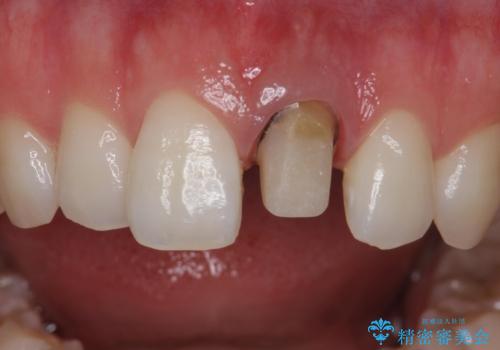

前歯が暗く変色 ジルコニアクラウンでの修復

- 前歯の変色を主訴に来院された患者様です。

より審美的な修復を行いたいとのことであったため、ジルコニアクラウンでの修復を行います。